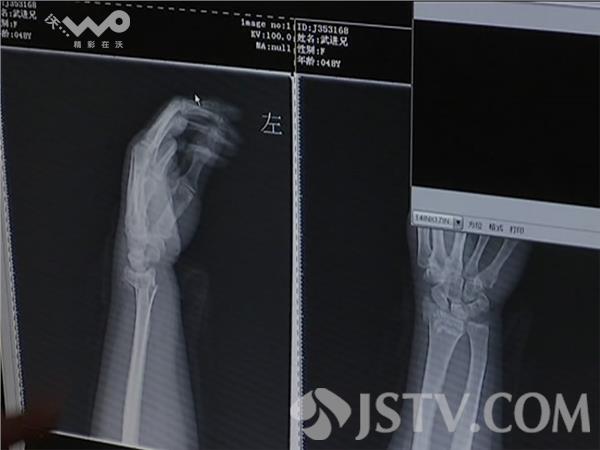

上午9点半,120急救车将一名骨折病人送往南京鼓楼医院急诊,38岁的周女士告诉记者,她一早出门准备到单位扫雪,没想到出门没多久,自己就摔倒了。采访中记者发现,从上午8点到中午,不断有摔伤骨折的病人被送往急诊外科,他们当中手腕部骨折居多,不少老年人还出现了髋关节骨折。南京鼓楼医院医学影像部秦民益告诉荔枝全媒体记者, 他从早上8点开始上班,到现在11点,总共为30位病人拍了片,大部分病人都是腕关节骨折。

根据120急救中心调度中心的统计,从今天凌晨截止到下午2点,因为摔伤骨折外伤向120急救中心求助的警情达到了68例。医生建议,老人小孩雨雪天气要尽量减少出门,以免意外发生。